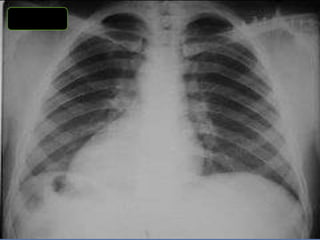

CRITERIOS DE EVALUACIONRX. TX.  Pulmones desde ápex hasta senos costo diafragmáticos  Pulmones y corazón sin rotación.  10 pares de costillas.  Sombra área de la tráquea centrada sobre la columna.  Balance en los contrastes de la imagen (exposición adecuada).

INTERPRETACION  Revisar estructuras óseas.  Partes blandas.  Espacios intercostales.  Parénquima pulmonar  Nivel de los senos costodiafragmaticos.  Neumatización.  Trama alveolo-pulmonar  Silueta cardiaca  Cayado aórtico.